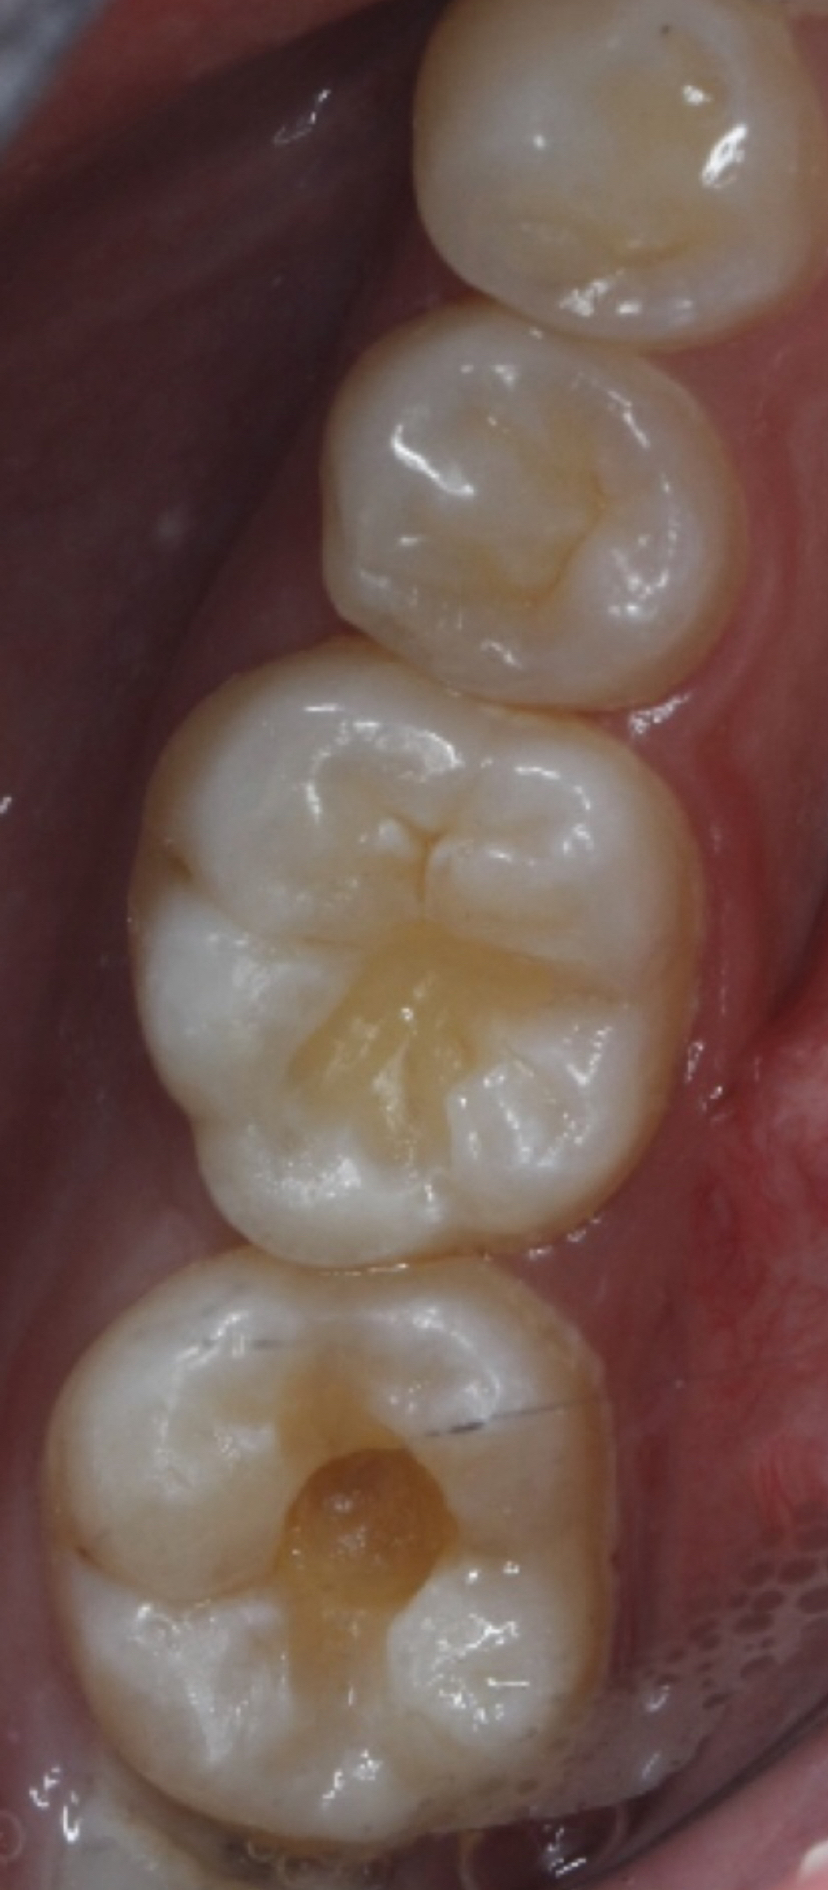

医生通过目视或X光片确定龋坏范围和深度。

用牙钻或激光去除蛀坏部分,确保剩余牙齿结构健康。

清洁窝洞后,填入补牙材料(如树脂、玻璃离子等),塑形并固化。

1. 复合树脂

- 优点:颜色接近真牙,美观耐用,适合前牙。

- 缺点:价格较高,强度略逊于银汞。